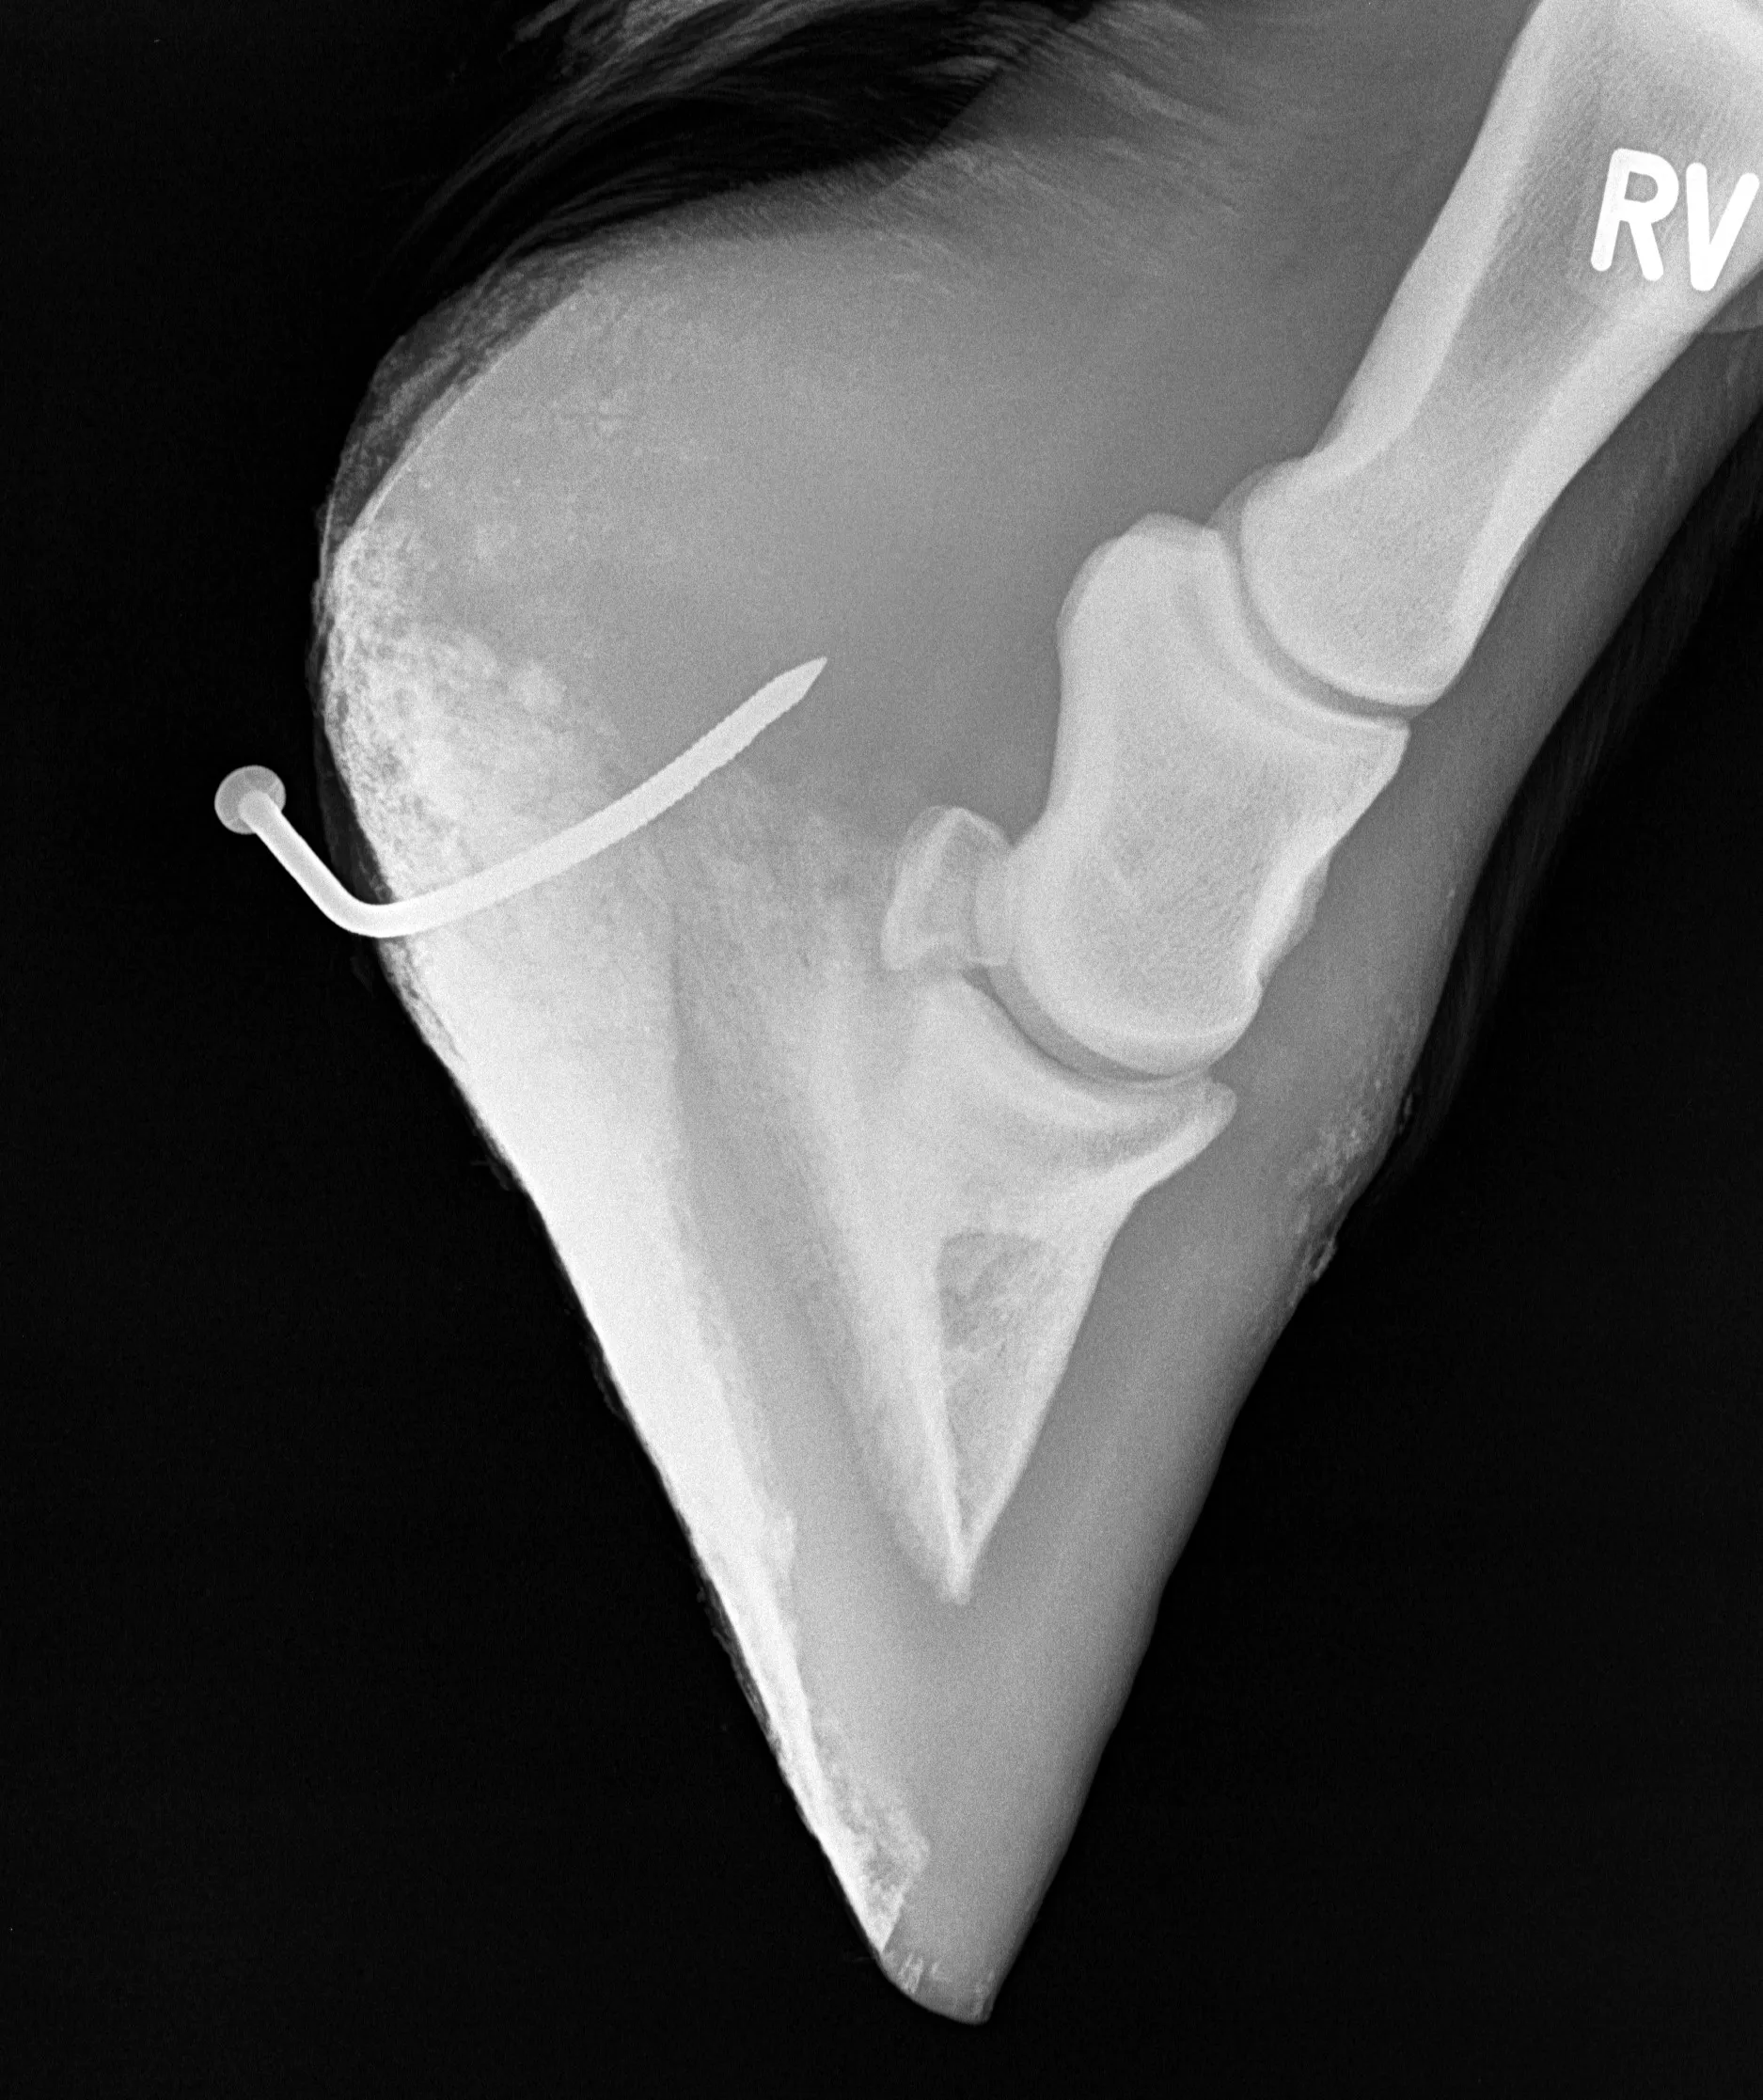

Durch die umfassende Ausstattung aller Ambulanzfahrzeuge ist es möglich, sofort und flexibel vor Ort zu reagieren. Dies ist besonders wichtig bei Notfällen an Atemwegen (wie z.B. Nasenbluten, Atemnot), Koliken (akuten abdominalen Schmerzen), Schnitt-, Stich- oder Bissverletzungen, Verletzungen an Gelenken, Geburten, aber auch bei akuten Lahmheiten oder Unfällen. Es steht eine umfangreiche Diagnostik, die schnelle Erstversorgung sowie gezielte Therapie zur Verfügung.

Mit den heutigen Möglichkeiten der Standnarkose und der lokalen Betäubung lassen sich frische Verletzungen unter Umständen auch vor Ort versorgen. Dies ist immer im Einzelfall abzuwägen. Darüber hinaus werden auch geplante kleinere chirurgische Eingriffe im Stall vor Ort durchgeführt. Dazu gehören das Entfernen von kleineren Hauttumoren oder auch Zähnen, sowie Lidrandoperationen oder Biopsien.